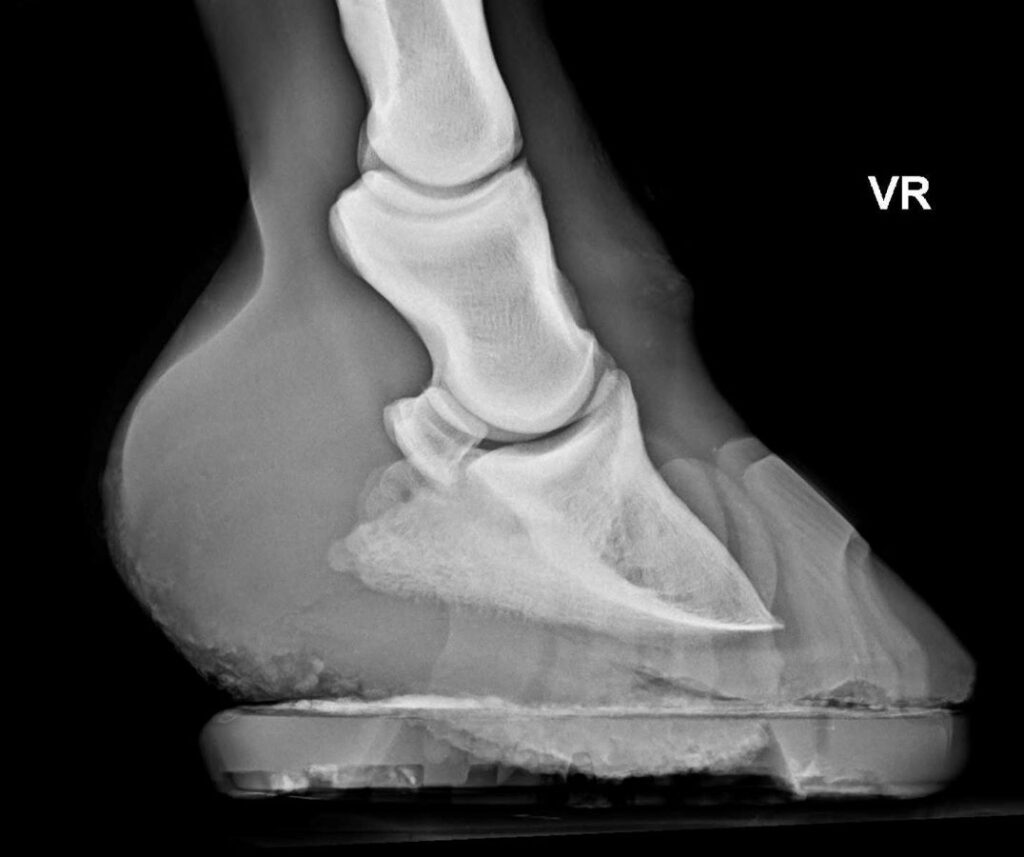

Zu einem Hufröntgen wird meist geraten, wenn Stellungsauffälligkeiten korrigiert werden sollen oder das Pferd unklare Lahmheiten zeigt, deren Ursprung im Huf vermutet wird. Doch Achtung: Ein Röntgengerät ist kein Zauberapparat, der automatisch die Wahrheit ausspuckt. Ein Röntgenbild ist immer nur eine zweidimensionale Projektion eines dreidimensionalen Objekts – vereinfacht gesagt ein „Schattenbild“ in verschiedenen Graustufen. Das macht die Interpretation anspruchsvoll: Strukturen überlagern sich, und Winkel können täuschen, wenn die Aufnahme nicht perfekt ausgerichtet ist. Schwierig machen es dabei nicht nur ungeduldige Patienten, sondern vor allem sogenannte Artefakte. Das sind Dinge auf dem Bild, die dort eigentlich anatomisch nicht hingehören, aber durch Dreck, Metall oder Bewegungsunschärfe sichtbar werden und eine Diagnose massiv erschweren können.

Wenn dein Pferd Hufeisen hat, ist es sehr ratsam, diese vor dem Röntgen von deinem Hufprofi abnehmen zu lassen. Ein Hufeisen auf dem Röntgenbild ist wie ein massiver Balken vor der Aussicht. Das Metall verursacht starke Streustrahlung, das Bild wird um das Eisen herum unscharf oder überbelichtet und natürlich verdeckt das Eisen auch Teile der relevanten Strukturen. Feine Details wie Haarrisse können so übersehen werden, der Hufbeinrand oder Teile des Strahlbeins werden verdeckt. Zudem verfälscht der Beschlag die Beurteilung der Sohlendicke. Für eine verlässliche Diagnose führt daher kein Weg daran vorbei: Das Eisen muss runter.